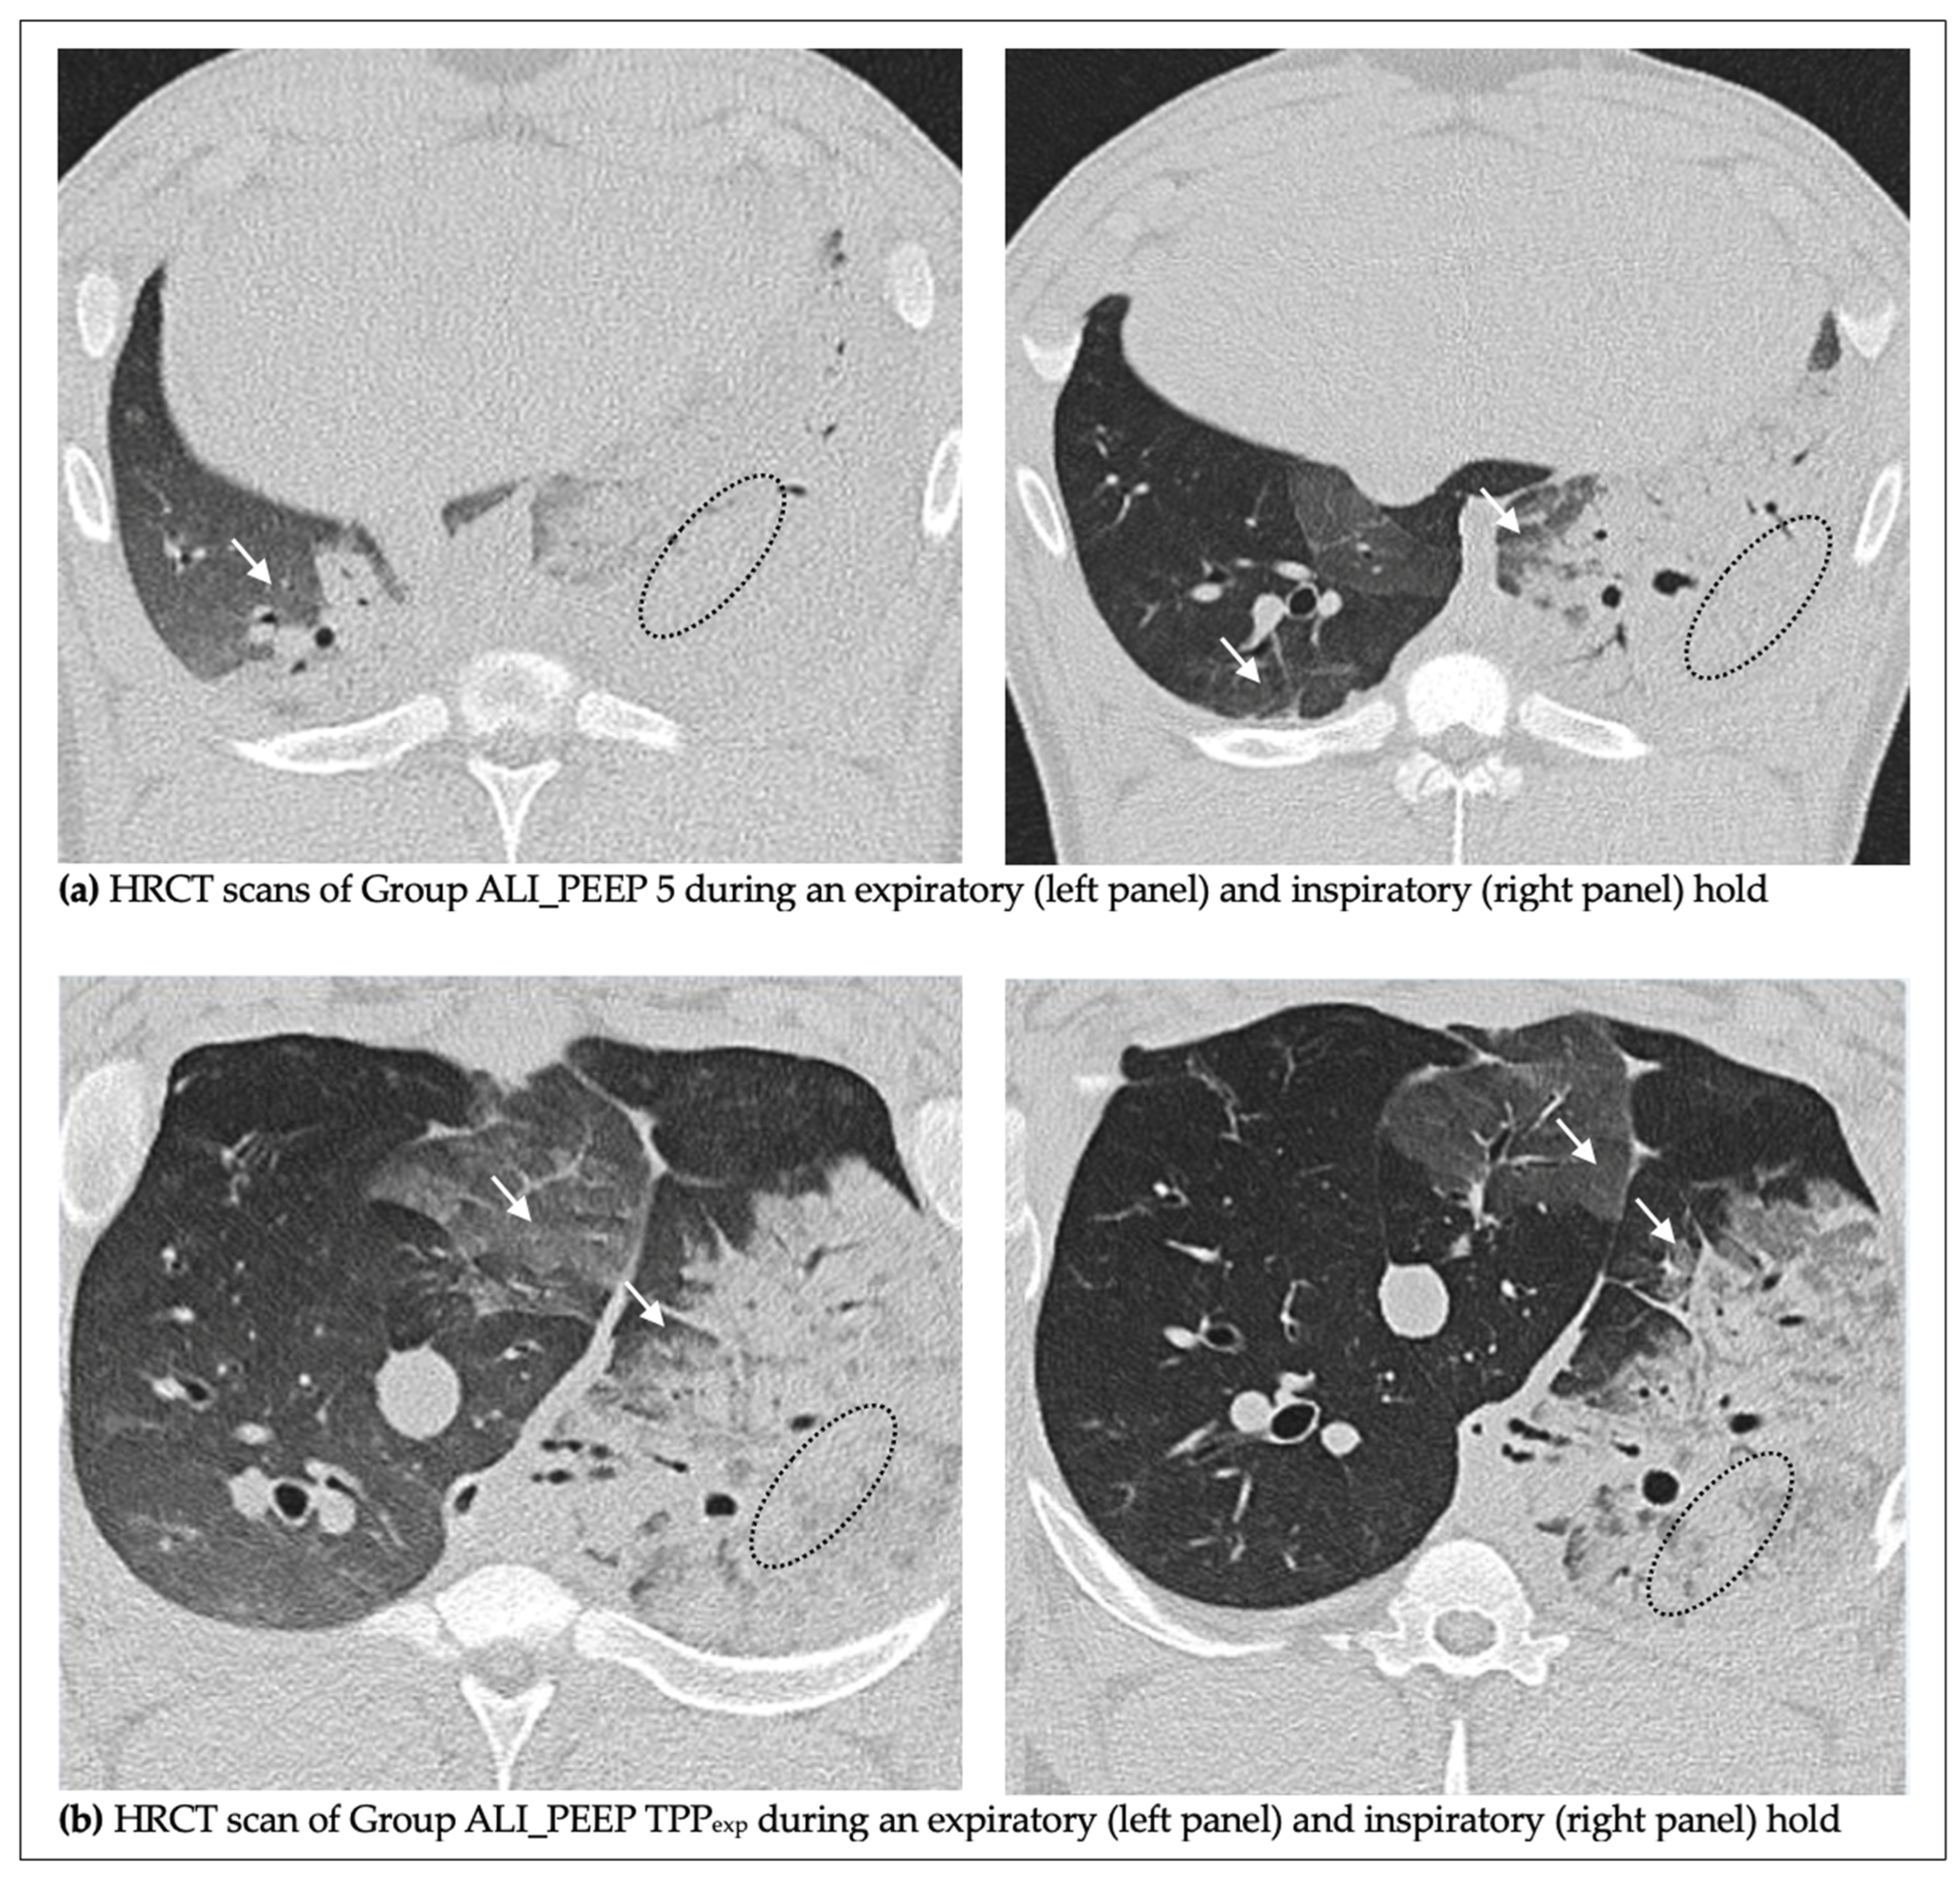

2.2. High-Resolution Computed Tomography Lung Injury Score

2.2.2. Expiratory vs. Inspiratory Hold

2.2.3. ALI_PEEP 5 vs. ALI_PEEP TPPexp

3.3. HRCT Findings

| Group | Lung Side | HRCT Score Expiratory Hold (5 cmH2O) | HRCT Score Inspiratory Hold (30 cmH2O) |

|---|---|---|---|

| ALI_PEEP 5 | Left | 262 ± 11 | 270 ± 35 |

| ALI_PEEP 5 | Right | 142 ± 7 * | 125 ± 4 *† |

| ALI_PEEP TPPexp | Left | 260 ± 12 | 268 ± 15 |

| ALI_PEEP TPPexp | Right | 121 ± 6 *‡ | 116 ± 8 *‡ |